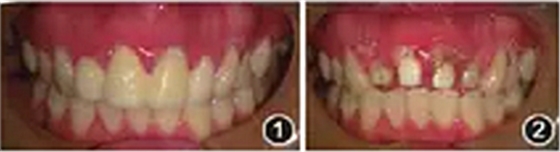

临时冠修复体,龈缘红肿,唇侧根尖区可见窦道口(图1)。去除临时冠后可见为桩冠预备体。可见白色氧化锆桩核,叩痛+~++,根尖区扪痛。冠部唇侧开髓洞型可见牙色充填物,叩痛+,根尖区扪诊无不适。探诊深度2~3 mm,无松动(图2)。

图1患者临时冠修复体,牙龈缘红肿,根尖可见窦道

图2患者氧患者化锆桩核,可见开髓洞型及牙色充填物